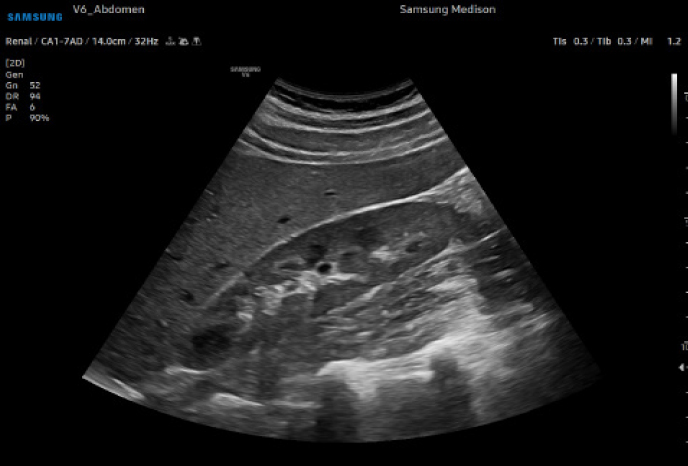

하이앤드 초음파 장비를

활용한 정밀 심장 검사

심장 질환 진단에서 가장 중요한 것은 ‘심장의 상태를 얼마나 정확하게 볼 수 있느냐’입니다. 저희 센터는 대학병원급 하이앤드 초음파 장비를 도입하여, 실시간 3D 렌더링으로 정밀 진단이 가능하며, 심장의 구조·혈류·기능을 실시간 고해상도로 관찰합니다.

미세한 판막 움직임, 혈류 속도 변화, 심방·심실 크기와 수축력까지 정밀하게 분석할 수 있어, 심장질환의 조기 발견과 치료 계획 수립에 큰 차이를 만듭니다.